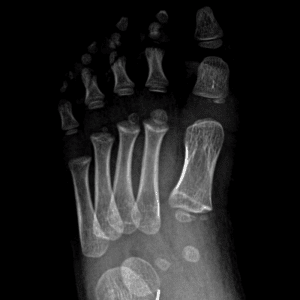

Pediatric Radiographs